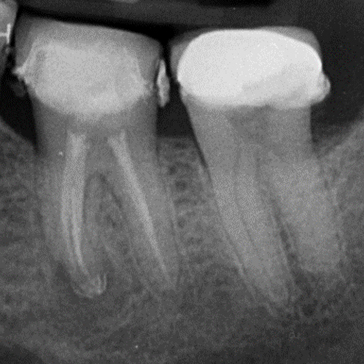

Case 3. Re-RCT of UR6